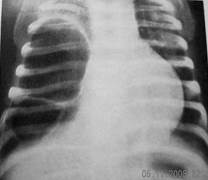

Осложнение врожденных кист распределяют таким образом: нагноение кисты - 60%, напряжение кисты - 20%, прорыв в плевральную полость - 5%. На кисты с бессимптомным течением приходится 15%. Нагноение кисты возникает в любом возрасте и сопровождается ухудшением общего состояния, повышением температуры тела до высоких цифр, интоксикацией, ознобом, лейкоцитозом. На рентгенограмме (Рис.12) обнаруживают полость круглой формы с уровнем жидкости.

Рис.12. Врожденная киста правого легкого с уровнем жидкости (нагноение)